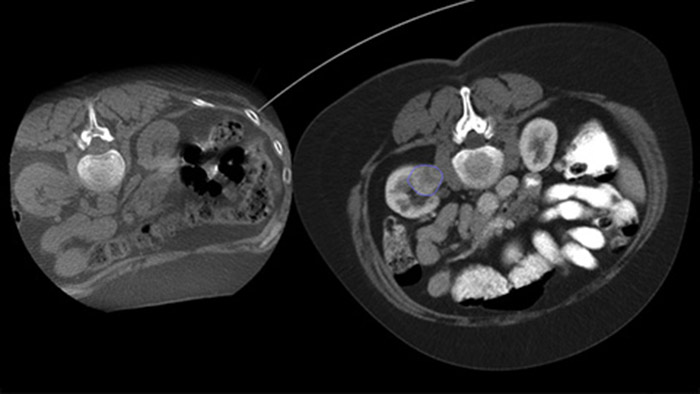

La ablación percutánea (radiofrecuencia, microondas y crioablación) es un tratamiento mínimamente invasivo bien establecido para los tumores de riñón, hígado, pulmón y hueso. Es fundamental definir los límites del tumor y decidir el número óptimo de agujas y la correspondiente trayectoria de estas para poder realizar un tratamiento completo del tumor y no causar daños en el tejido circundante. Navegar con precisión con baja dosis hasta la lesión de interés sin reposicionar la aguja aumenta las posibilidades de éxito y reduce el riesgo de complicaciones de las biopsias o ablaciones. La confirmación del punto final del tratamiento de ablación puede realizarse con imágenes en 3D mientras el paciente sigue en la mesa.

Adquiera una THC posterior a la ablación para demostrar la extensión de la cobertura del tumor y confirmar la finalización de su tratamiento.